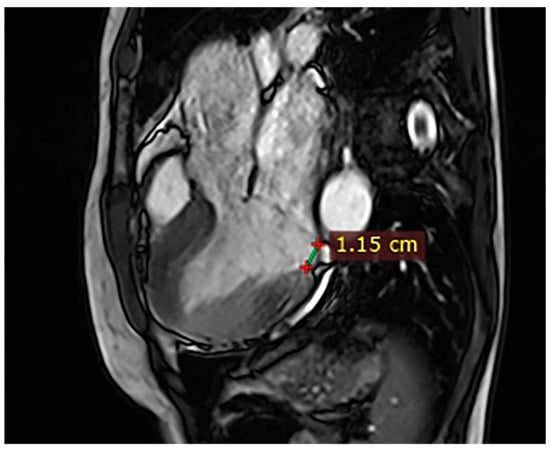

| Case | Patient (Sex, Age) | Symptoms | MAD (mm) | Valvular Issues | LGE | Other Details |

|---|---|---|---|---|---|---|

| 1 | Female, 61 years old | Syncope | 11 | MVP, mitral regurgitation | Lateral | Holter: atrial tachycardia and ventricular ectopy; cardiology follow-up planned for possible mitral valve repair |

| 2 | Male, 52 years old | Syncope and atypical chest pain | 10 | - | Lateral | History of ventricular arrhythmias; cardiology follow-up and Holter monitoring recommended |

| 3 | Female, 74 years old | Extrasystole | 3 | - | No LGE | No LGE; patient reassured and scheduled for periodic clinical follow-up |

| 4 | Male, 34 years old | Extrasystole in Marfan syndrome | 15 | MVP, valvular regurgitation | No LGE | Marfan syndrome; MVP with regurgitation; regular cardiology follow-up advised. |

| 5 | Male, 63 years old | Heart failure | 2,5 | MVP, valvular regurgitation | No LGE | Reduced LVEF (47%) with left atrial dilatation; heart failure therapy optimized; follow-up planned. |

| 6 | Male, 68 years old | Palpitations | 5 | - | Lateral | LGE in basal lateral wall; electrophysiological evaluation and ECG monitoring recommended. |

| 7 | Female, 53 years old | Extrasystole and syncope | 15 | MVP, valvular regurgitation | Basal-lateral | Extensive MAD with MVP and LGE; increased arrhythmic risk; antiarrhythmic therapy considered. |

| 8 | Female, 63 years old | Aortic and mitral regurgitation | 11 | Aortic and mitral regurgitation | Lateral | Aorto-mitral regurgitation with septal hypokinesia; mitral valve repair performed; heart failure therapy started. |

| 9 | Male, 45 years old | Palpitations and vertigo | 10 | - | Lateral | Basal lateral LGE; regular clinical and ECG follow-up recommended |